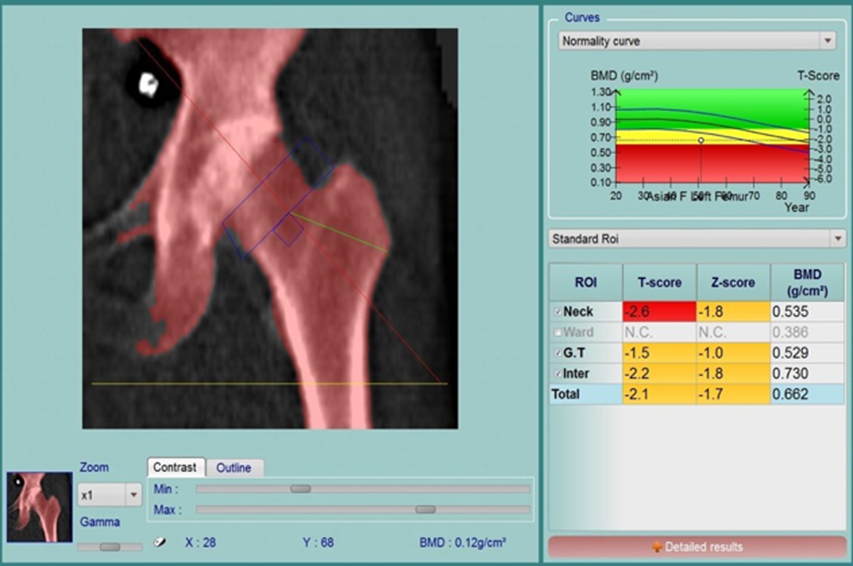

4.2 Một số hình ảnh kết quả đo loãng xương ở BVĐK tỉnh Quảng Trị

Kết quả tình trạng Loãng xương (Osteoporosis) với T-score ≤ – 2,5SD

Kết quả: Tình trạng Thiếu xương (Osteopenia) ở bệnh nhân này với T-score nằm giữa – 1,0 SD đến – 2,5 SD và Loãng xương (Osteoporosis) với T-score ≤ – 2,5SD ở một số vị trí